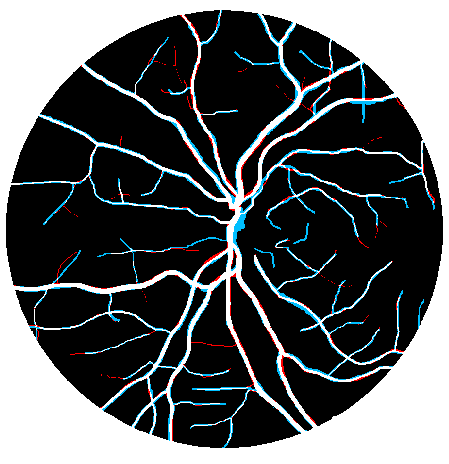

The Sn, Sp, Acc, and AUC values of the best case for the DRIVE database were 0.9119, 0.9742, 0.9667, and 0.9903, while those of the worst case matched 0.7628, 0.9816, 0.9497, and 0.9786, respectively (Fig. 6(a)). For the STARE database, the values of the best case were 0.8527, 0.9936, 0.9837, and 0.9964, while those of the worst case matched 0.7231, 0.9827, 0.9503, and 0.9791 (Fig. 6(b)). Finally, for the CHASE_DB1 database, the values of the best case were 0.8541, 0.9844, 0.9744, and 0.9909, while those of the worst case matched 0.8065, 0.9749, 0.9574, and 0.9808 (Fig. 6(c)).

By jointly evaluating Sn, Sp, and Acc, our method presented the best performance on both the DRIVE and CHASE_DB1 databases. In the DRIVE database, we outperformed all the other works regarding Sn and Acc. In terms of Sp, we stood in sixth; however, knowing that Acc combines information from Sn and Sp, we may conclude that the gain in true detections was much more significant than the inclusion of false detections. In other words, there is a notorious trade-off between Sn and Sp, with our method having a better balance. In the CHASE_DB1 database, we ranked first in all metrics. Regarding the STARE database, we ranked second in all metrics, only behind Neto et al., (2017) in Sn and Liskowski and Krawiec, (2016) in Sp and Acc. By comparing our work with (Neto et al.,, 2017), we see that our Sp is much higher so, given the trade-off abovementioned, the slight disadvantage in terms of Sn sounds natural. In parallel, if we consider the second row of Fig. 6(b), which shows our worst case, we notice that our method failed in rejecting small haemorrhagic blobs, which may have affected Sp. This may be explained by our choice of using 5-fold cross-validation for training, which reduced the number of images with pathological signs, contrary to (Liskowski and Krawiec,, 2016), which used leave-one-out cross-validation.

Except for the STARE database, in both the remaining databases there is no clear difference between the marking pattern of the experts. That is, we can see cases where the first observer marks vessels that the second one does not see and vice versa. This may be deduced from Fig. 7, where we compare the annotations of both observers, for each database. We believe that this noticeable discordance may become a limiting factor for future improvements since the current results of this field are already extremely accurate.